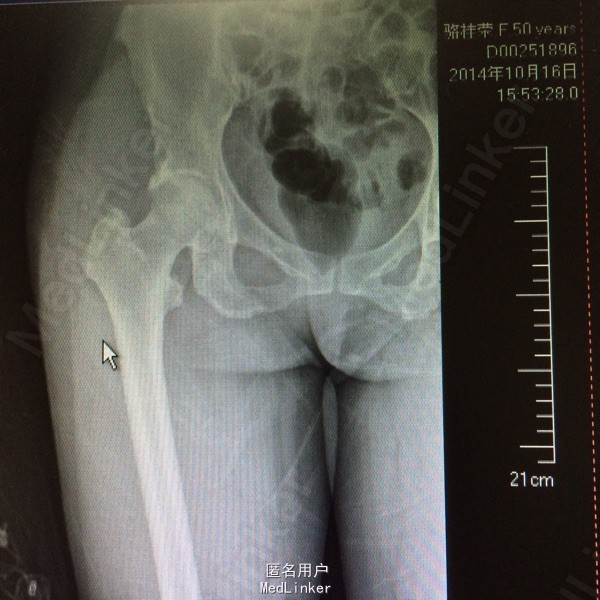

患者,女,50岁。因“双髋关节疼痛活动受限一年余”入院。 患者一年余前无明显诱因感双髋关节疼痛,活动后症状加重,休息后稍有缓解,不伴发热、咳嗽,否认明确外伤史。于今年8月在我院门诊拍片(M00085020)示:双侧股骨缺血性坏死。今为求进一步治疗来我院求诊,门诊查体阅片后以“双侧股骨头缺血性坏死”收住我科。 自起病以来,患者饮食睡眠可,二便正常,体力下降,体重无明显改变。 既往:否认肝肾病史,否认食物、药物过敏史

体格检查:T 36.8℃ P 78次/分 R 20 次/分 BP 142/96mmHg,神志清醒,平静面容,扶拐跛行步入病房,查体合作。发育正常,全身皮肤未见黄染,浅表淋巴结未及肿大,头颅无畸形,双侧瞳孔等大等圆,光反射灵敏。颈软,胸廓无畸形,双肺呼吸音清晰,未闻及干湿性啰音。心律齐,各瓣膜听诊区无杂音。腹平软,无压痛反跳痛,脊柱无畸形,各棘突无压痛。双上肢正常。 专科情况:双髋关节未见明显肿胀,腹股沟中点处深压痛,下肢无轴向叩击痛,双髋关节活动度因疼痛减小,4字征阳性,双足背动脉搏动可及,各趾感觉、活动正常,直腿抬高试验阴性,双下肢无明显短缩。 门诊资料:我院MRI(M00085020)示:“双侧股骨头缺血性坏死”。

初步诊断:双侧股骨头缺血性坏死 鉴别诊断:X线片上未见骨肿瘤,骨囊肿等征象可与肿瘤相相鉴别,具体有待于进一步检查。 诊疗计划:1.卧床休息,暂不负重,对症支持处理。 2.完善相关检查(血、尿分析、肝肾功能、骨盆平片、髋关节CT、胸片ECG、心脏彩超等)。 3.择期手术治疗(髋关节置换术)。